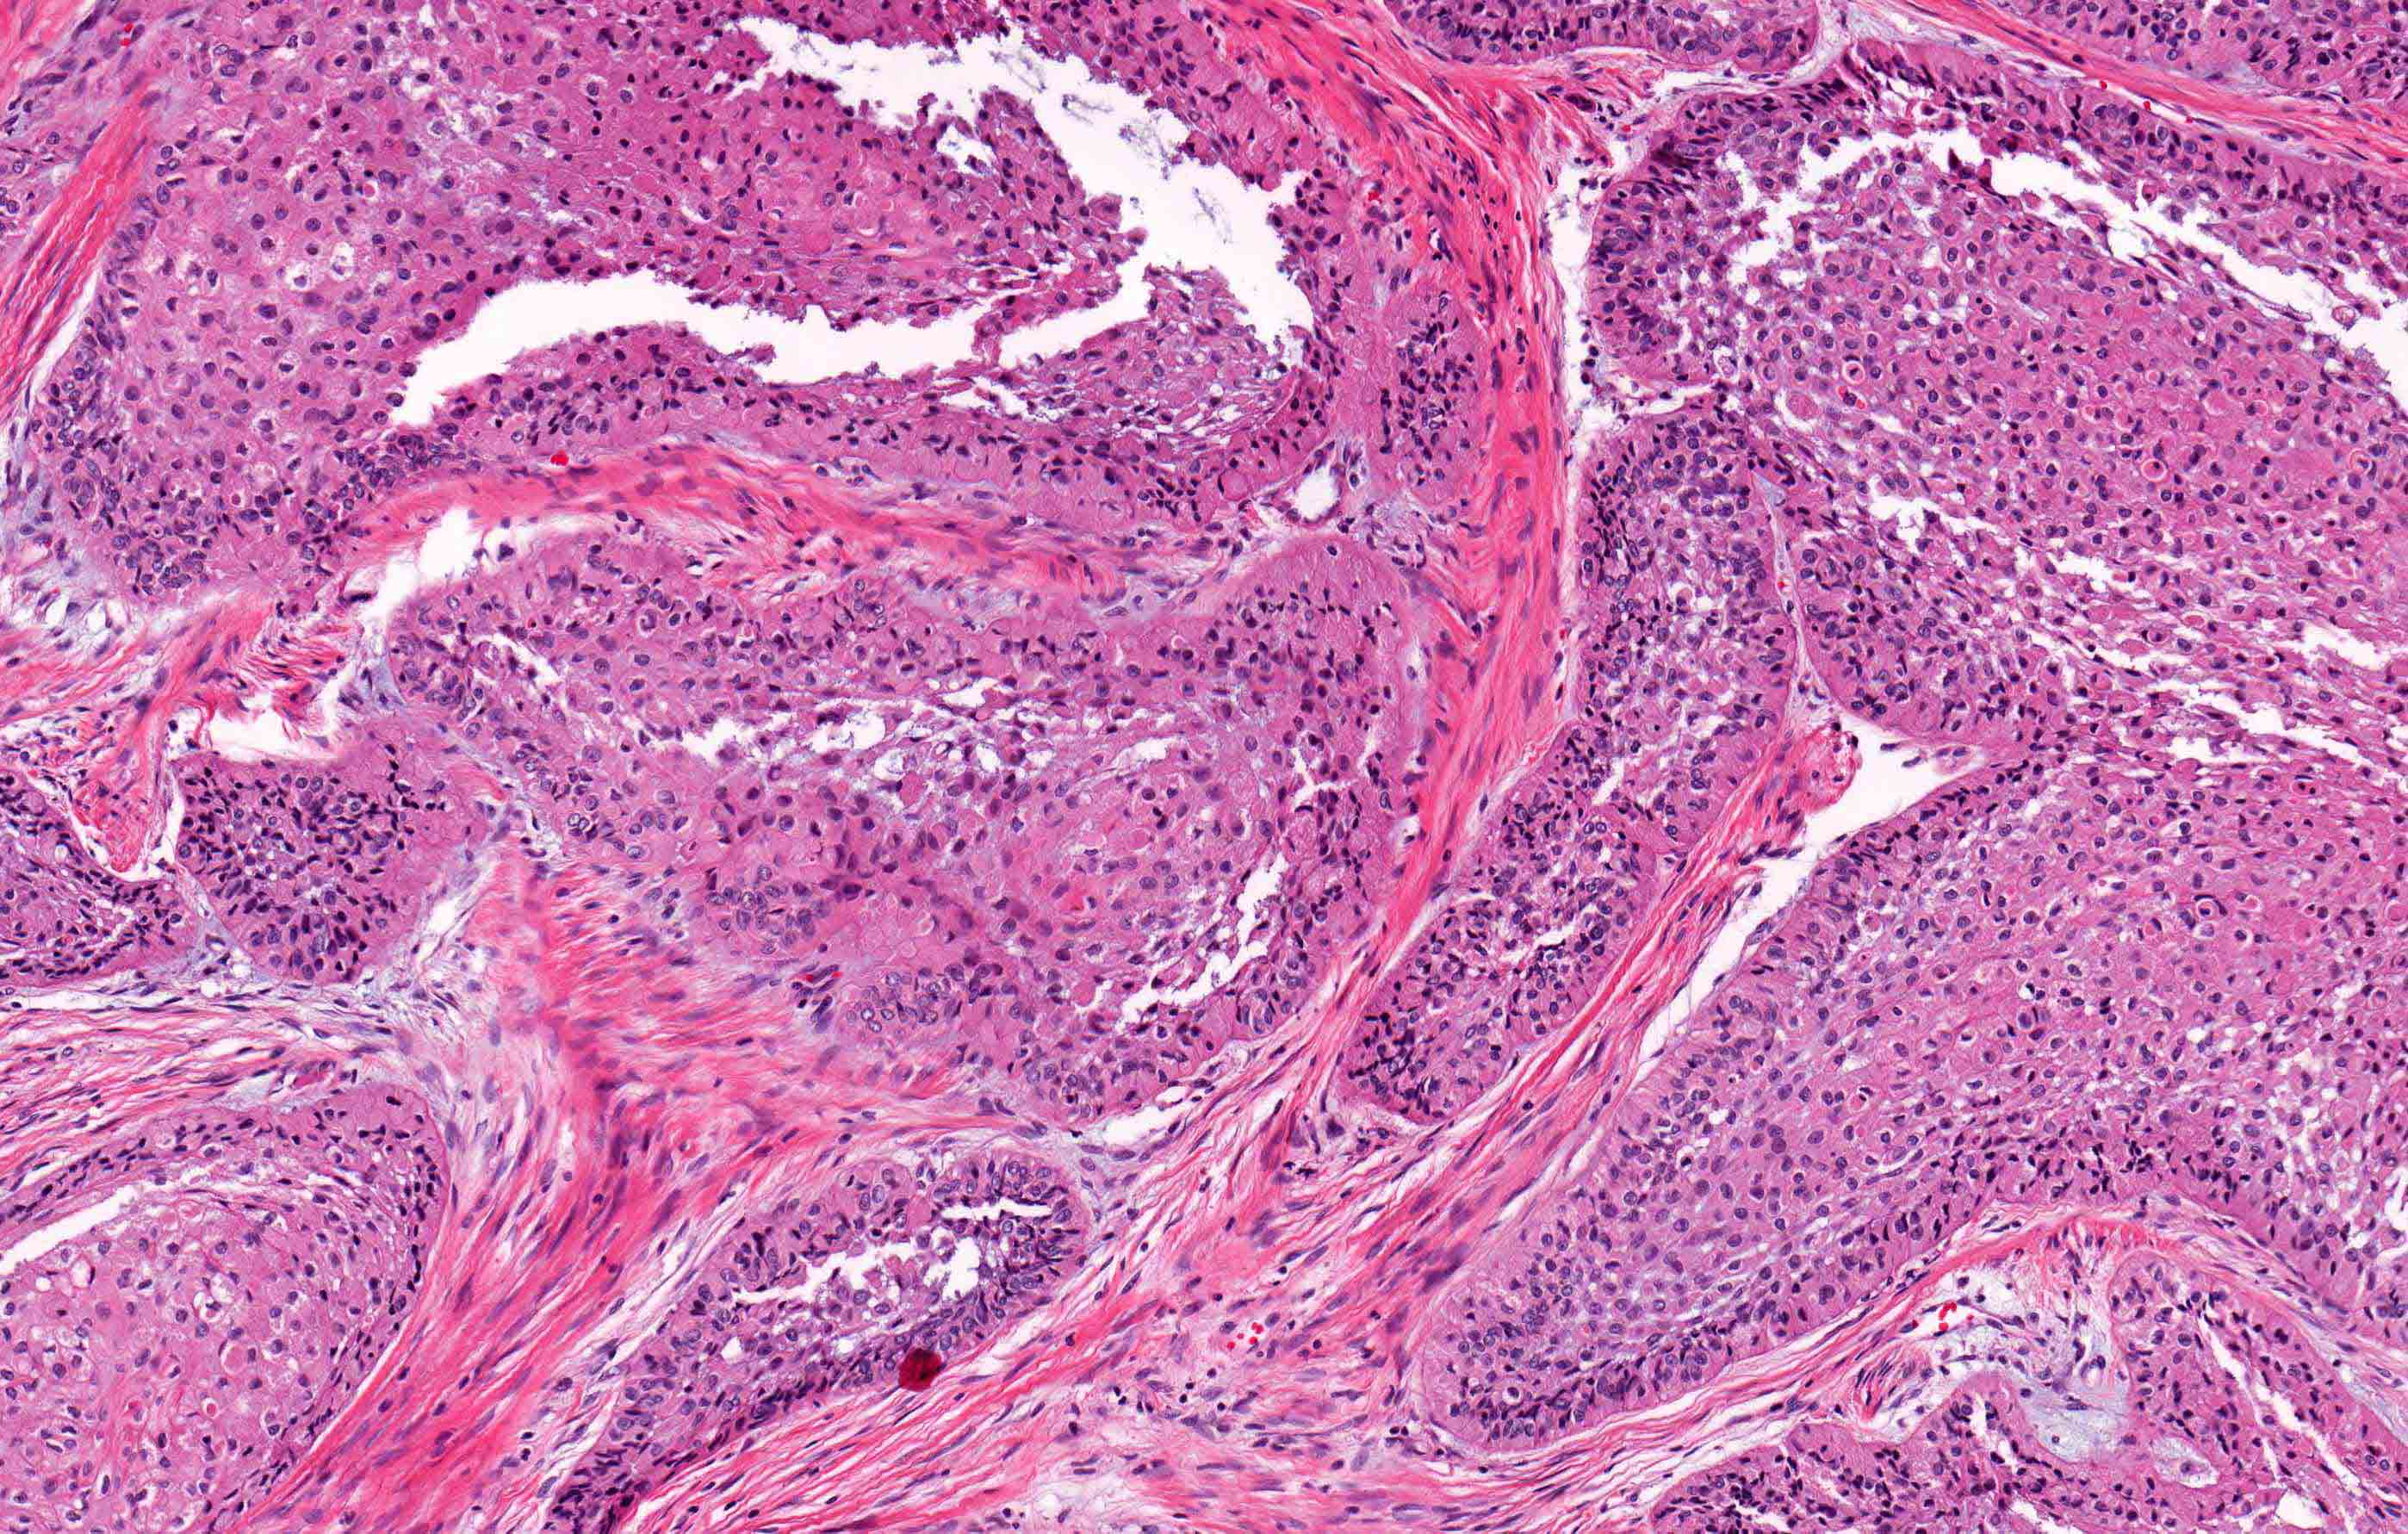

Microscopic (histologic) description

- Within the epithelial islands and cords of conventional ameloblastoma and the cystic epithelial lining of unicystic ameloblastoma, the odontogenic epithelium shows similar changes:

- Columnar cells with hyperchromatic nuclei at basal layer, exhibiting peripheral palisading

- Cells show reverse polarization away from basement membrane (Vickers-Gorlin change)

- Subnuclear vacuolization

- Suprabasal cells with a loose, network-like arrangement, recapitulating stellate reticulum formation seen in normal odontogenesis

- No dentin or enamel formation

- Ameloblastoma, conventional type has at least 6 histopathological patterns

- Single patterns may predominate within a given lesion, often mixed with 1 or more patterns

- Microscopic pattern has no documented prognostic significance

- Follicular: most common subtype; islands of odontogenic epithelium in fibrous connective tissue; may be cystic; classic peripheral palisading and stellate reticulum-like areas

- Plexiform: cords and sheets of anastomosing odontogenic epithelial cells; classic peripheral palisading and reverse polarity not always obvious

Microscopic (histologic) images

Contributed by Kelly Magliocca, D.D.S., M.P.H. and Anne C. McLean-Holden, D.M.D., M.S.